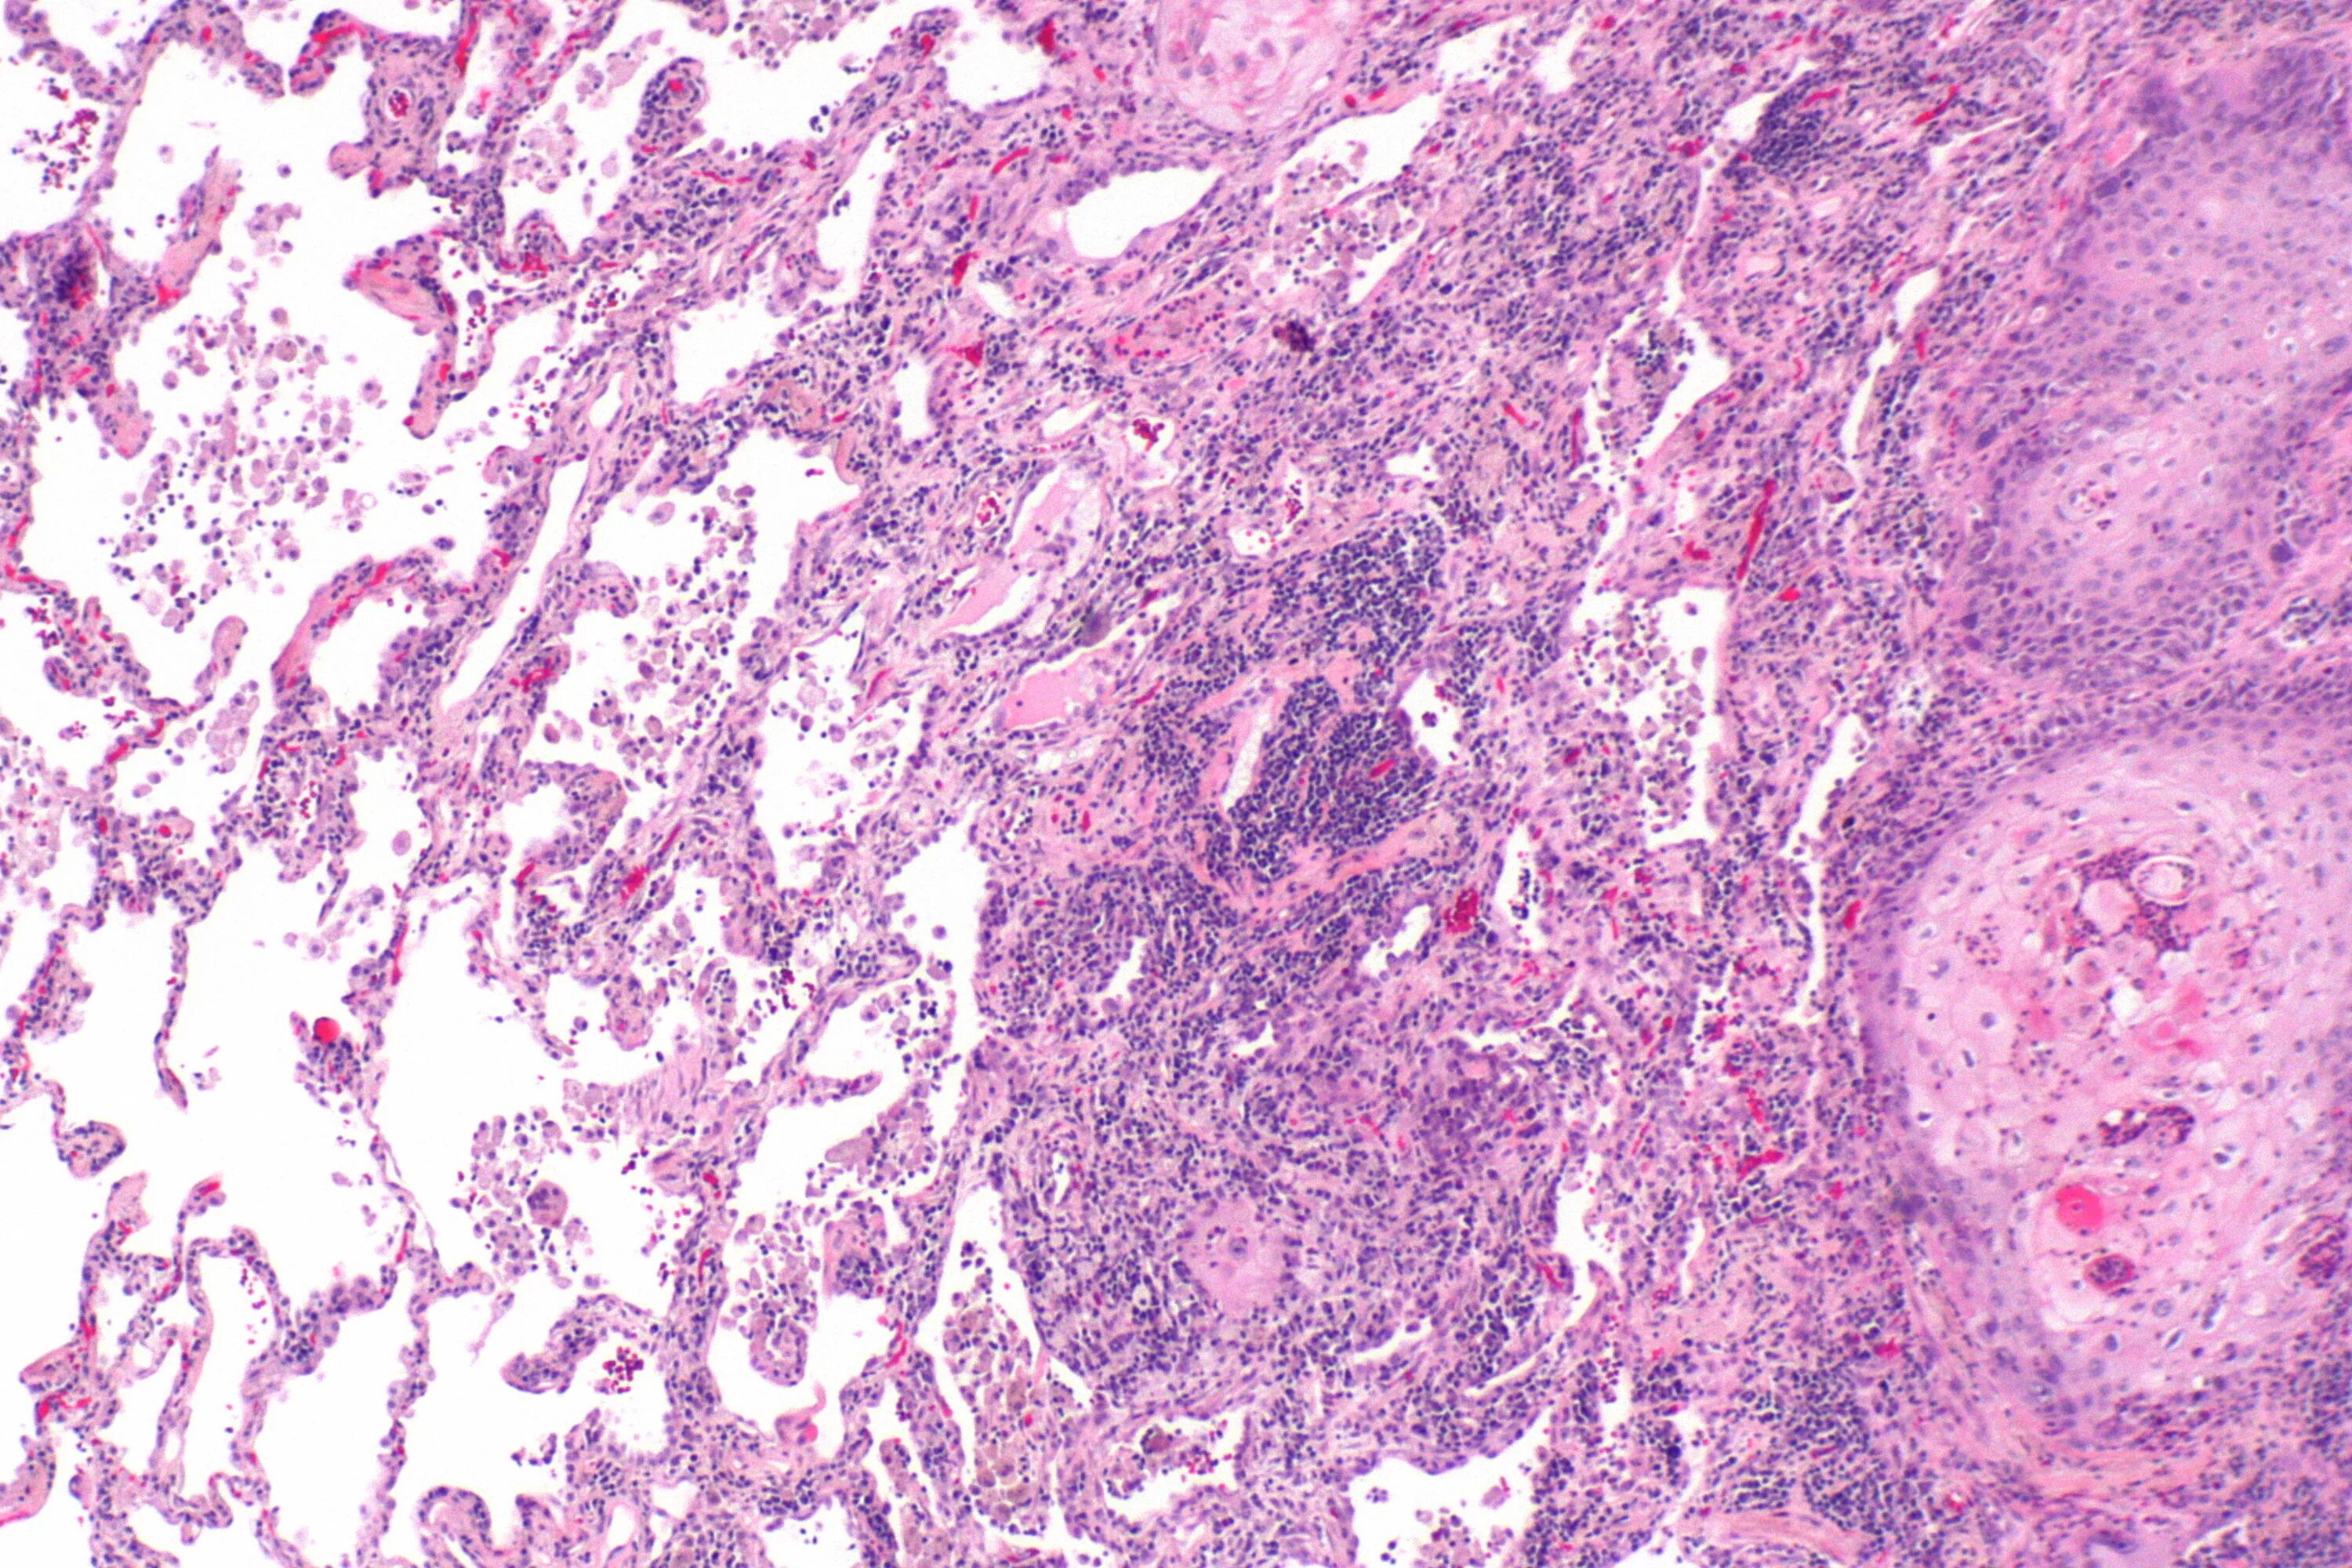

Высокодифференцированная аденокарцинома кишки